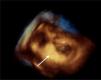

Case reportAn 84-year-old woman, with a history of hypertension and dyslipidemia, was admitted to our institution because of an intracardiac mass. She described a five-month history of shortness of breath on exertion (NYHA functional class III) and peripheral edema. Physical examination revealed a grade III/VI mitral systolic murmur. The electrocardiogram was unremarkable. Laboratory tests results showed no significant alterations. The transthoracic echocardiogram demonstrated a large, round, heterogeneous, echodense mass at the base of the posterior leaflet (Fig. 1). Doppler examination documented severe mitral regurgitation. The three-dimensional transthoracic echocardiogram revealed the mass involving the posterior mitral annulus, distorting it into a more triangular shape (Fig. 2). Three-dimensional transthoracic color flow imaging showed an eccentric mitral regurgitation jet originating from the posteromedial commissure (Fig. 3). The transesophageal echocardiogram confirmed the location of the mass and severe mitral regurgitation (Fig. 4), with two jets identified, one central and the other eccentric, apparently originating from the posteromedial commissure. Cardiac magnetic resonance (CMR) imaging was performed to better evaluate the mass. This showed a hypointense mass in the posterior region of the mitral annulus/basal segment of the inferior wall (Figs. 5 and 6). Rest perfusion CMR demonstrated hypoperfusion of the mass compared to normal myocardium (Fig. 7). Phase-sensitive inversion-recovery CMR showed late gadolinium enhancement in the peripheral margin of the mass (Fig. 8). On the basis of the above findings, a presumptive diagnosis of a centrally liquefied mass containing a high-protein or hemorrhagic content with an inflammatory and/or fibrotic wall was made. A multislice computed tomography (CT) scan of the heart was also performed, demonstrating a relatively homogeneous, high-density mass with foci of calcification (Figs. 9 and 10). A multi-modality imaging approach confirmed the diagnosis of caseous calcification of the posterior mitral annulus.

DiscussionCCMA is a rare evolution of mitral annular calcification.2,3 Echocardiography typically identifies this entity as a round, calcified, echogenic mass.4 CMR reveals a mass between the posterior mitral annulus and adjacent myocardium, with no enhancement after contrast administration and with strong peripheral enhancement 10 minutes after gadolinium administration with the use of the contrast-enhanced inversion-recovery technique.5 CT confirms the calcified aspect of the mass. Histological examination of the inner fluid usually reveals an amorphous, basophilic content, composed of a putty-like admixture of fatty acids, cholesterol, calcium and inflammatory cells, mainly macrophages.4,6 Early recognition of this entity avoids an invasive diagnostic approach, since it is benign and, unlike intracardiac tumors and abscesses, has a favorable prognosis.7 Surgery should be reserved for cases with severe co-existent mitral valve dysfunction, originating from compromised mitral leaflet coaptation secondary to mitral annulus distortion due to CCMA. There are brief references in the literature to possible spontaneous resolution of this entity.8,9 CCMA may rarely be associated with heart rhythm disturbances and systemic embolism.10